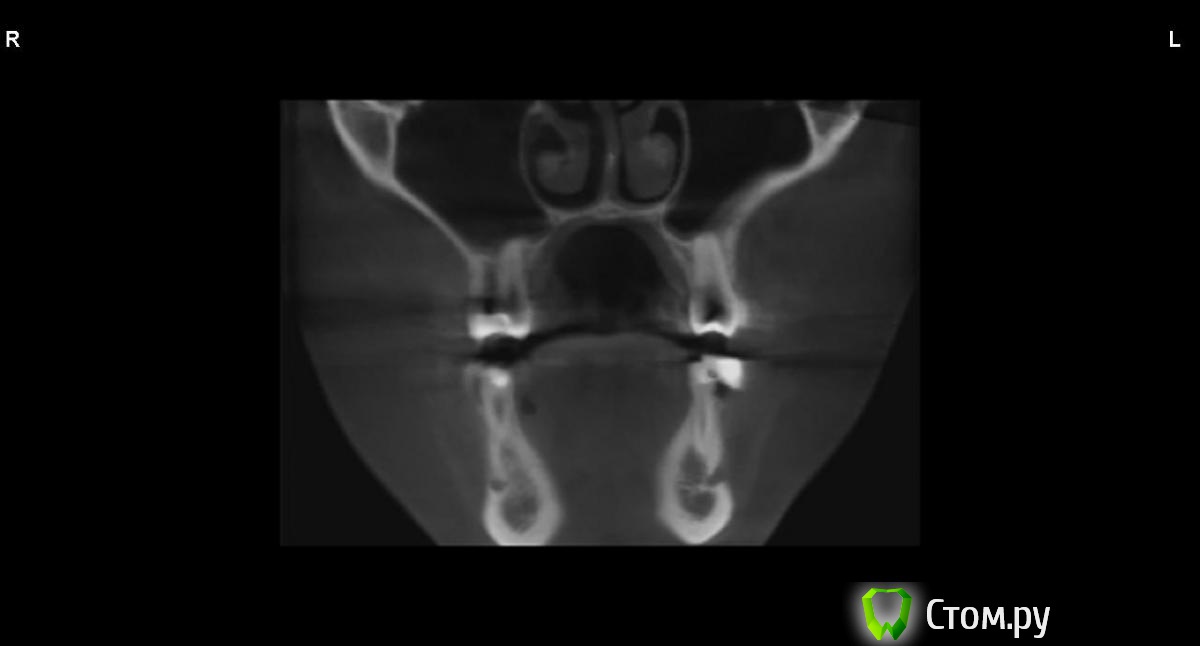

jm3300 Опубликовано 9 сентября, 2014 Автор Поделиться Опубликовано 9 сентября, 2014 вот, набросал Ссылка на комментарий

АнтонТЛТ Опубликовано 9 сентября, 2014 Поделиться Опубликовано 9 сентября, 2014 (изменено) это нижняя носовая раковина, возможно Изменено 9 сентября, 2014 пользователем АнтонТЛТ Ссылка на комментарий

АнтонТЛТ Опубликовано 9 сентября, 2014 Поделиться Опубликовано 9 сентября, 2014 я понял что это)))это артефакт от зуба, обратите внимание на правую сторону, там в пазухе тоже зуб есть, после эндодонтии)) Ссылка на комментарий